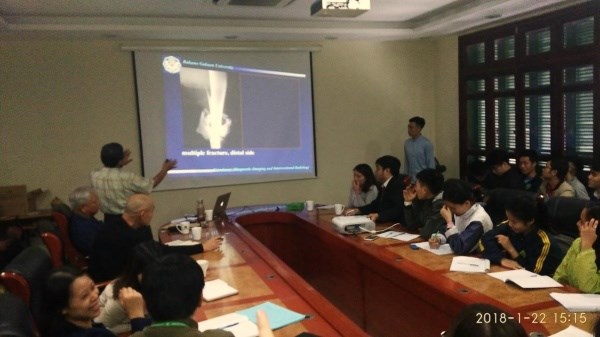

| TS. Minami Shigeru, GS. Tetsuya Nakade Rakuno, Trường Đại dafabet khuyến mãi Gakuen chia sẻ về ứng dụng chẩn đoán hình ảnh trong chẩn đoán và điều trị gãy xương ở chó, mèo tại Bệnh viện Thú y, dafabet khuyến mãi viện Nông nghiệp Việt Nam (22/01/2018) |